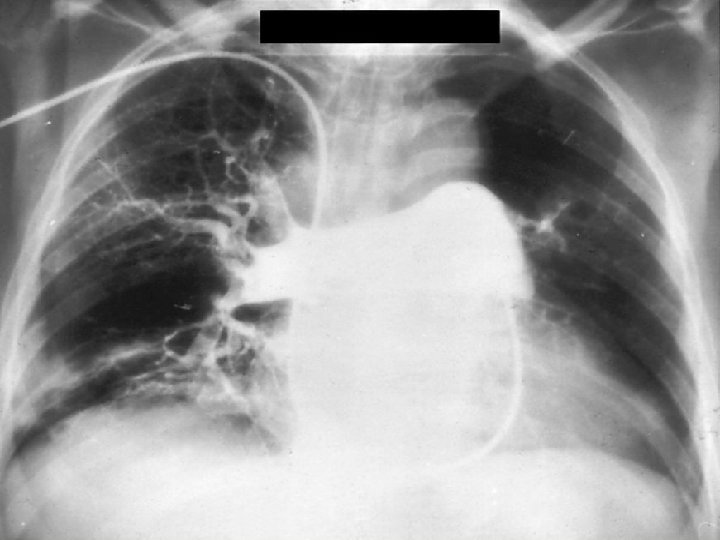

Chest X-ray and ECG X-ray Wide PA Elevated diaphragm Pleural fluid Wide RA vagy RV Infiltrate Atelectasia Local oligemia % 50 44 23 17 16 13 6 ECG ST depression Sinus tachycardia Negative T in V 2 -3 SV arrhythmia SI, QIII, negativ TIII RBBB P-pulmonale % 50 44 23 17 16 13 6

Acute, massive PE rs. R’